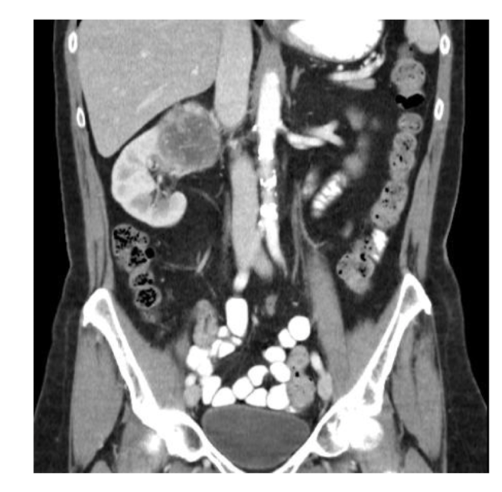

CT protocol + pathology

• Quad Phase Renal CT

• Path = hydronephrosis: swelling of the

kidney and ureters caused by a blockage

in the path of urine.

• Significant dilation of kidneys

• Hyperattenuating calculi causing the

occlusion of the path of urine from the kidney to bladder.